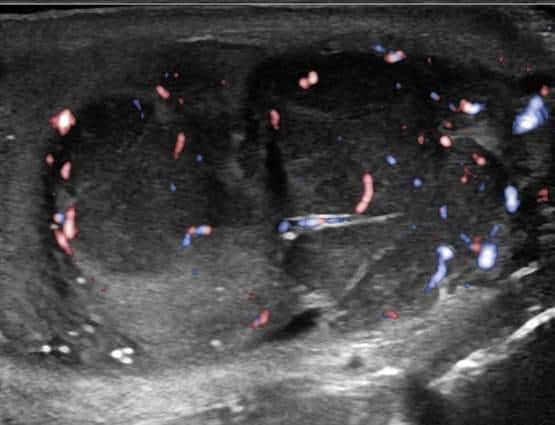

U tinh hoàn

» Thông tin: Nam giới – 28 tuổi.

» Lâm sàng: Sưng tinh hoàn.

# U tinh bào (Seminoma).